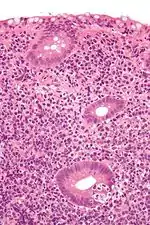

Micrograph showing a lymphoepithelial lesion (lower right of image) in a primary gastrointestinal tract lymphoma. H&E stain.

It may refer to a benign lymphoepithelial lesion of the parotid gland or benign lymphoepithelial lesion of the lacrimal gland, or may refer to the infiltration of malignant lymphoid cells into epithelium, in the context of primary gastrointestinal lymphoma.[1]

In the context of GI tract lymphoma, it is most often associated with MALT lymphomas.[1]